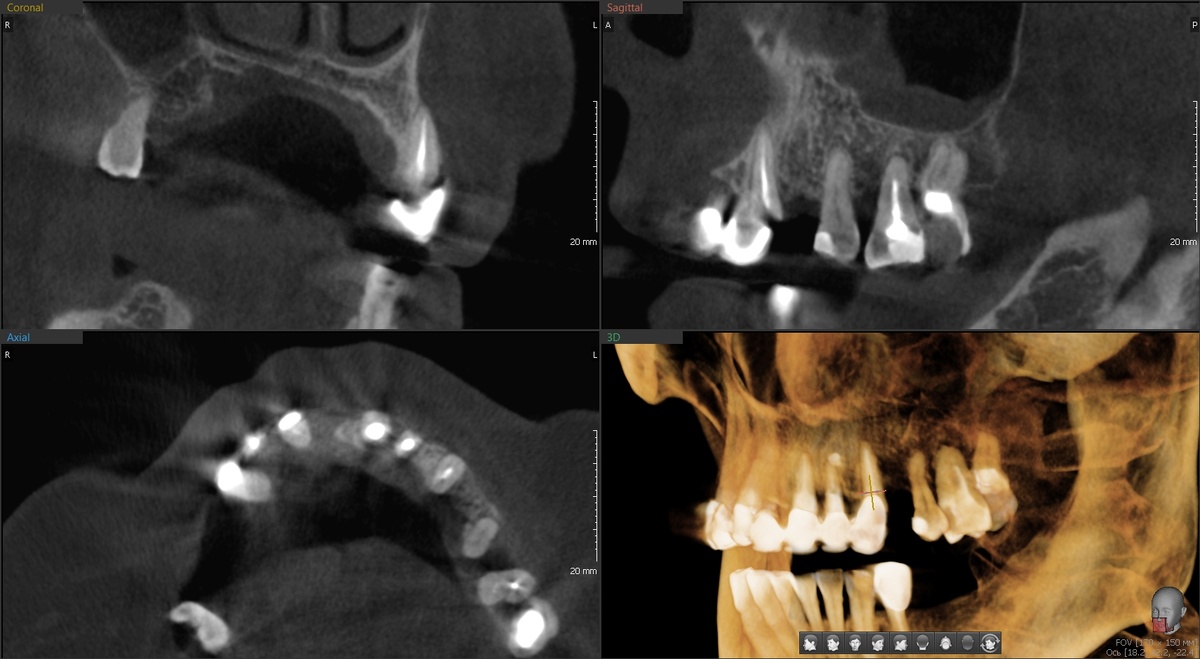

План такой - установить 4 классических имплантата + 2 птеригоидных (крыловидных) в дистальных отделах верхней челюсти. Птеригоидные - это такие длинные имплантаты (20-25 мм), которые проходят через всю челюсть и фиксируются в крыловидном отростке клиновидной кости. Надёжный способ избежать синус-лифтинга при атрофии для данного клинического случая.

Удалили остатки зубов на верхней челюсти, установили птеригоидные имплантаты, которыетребуют ювелирной точности. Сверлим под углом 45 градусов, проходим через толщу кости, целимся в крыловидный отросток. Промах на миллиметр - и можем попасть в крыловидное венозное сплетение или повредить нерв.

Но шаблон, спланированный в цифре, не даёт промахнуться. Два птеригоидных встали идеально.

Затем, по шаблону, установили 4 остальных имплантата - классика:

Проверяем стабильность "Пингвином" - все 6 имплантатов показывают отличный торк. Можно сразу нагружать имплантаты протезом.